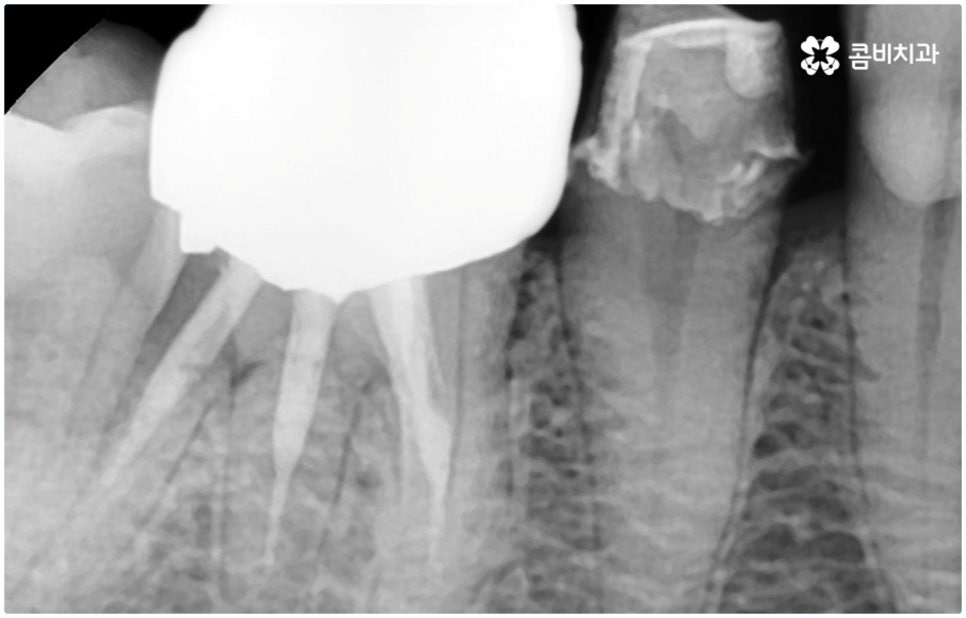

예를 들어 충치가 악화되어 세균이 치아 내부 치수 조직까지 침투한 경우 감염된 신경을 깨끗하게 제거하고 신경관 내부를 생체친화 충전재로 밀봉한 후 크라운으로 덮어 씌워주는 신경치료를 하게 되는데, 이때 감염 부위가 제대로 제거되지 않거나 2차 감염이 일어나 손상이 치아 뿌리까지 진행되면 자연 치아를 살리는 게 어려워 질 수 있습니다. 시기를 놓치면 재신경치료, 치근단 절제술 등의 보존 치료 역시 소용이 없어질 수 있으니 만약 신경 치료를 받은 치아가 있다면 더욱 신경써서 위생 관리에 주의하시고 검진을 통한 관리를 게을리 하지 않으시길 권유드리고 있어요.

그렇기 때문에 무조건 보다 빠르고 간편하다고 해서 원데이임플란트 방법을 고집하기 보다는 개인 상태에 따라 필요한 과정을 세심하게 맞춤 진행할 수 있도록 경험이 풍부하고 노하우가 뛰어난 의료진에게 치료 받는 것이 중요한 거예요. 즉 3D CT 등 정밀 검진 장비를 이용하여 환자분들의 치아 및 잇몸 상태, 치아 배열과 교합상태, 주변 치아와의 관계 및 조화까지 꼼꼼하게 파악할 뿐 아니라 턱뼈, 혈관, 신경 등 구강 전체를 함께 분석한 후 체계적인 시술 계획을 세워 각자에 맞는 방법으로 무리하지 않게 수술을 진행할 수 있는 숙련된 의료진과 함께 하는 것이 무엇보다 중요하다고 할 수 있습니다.